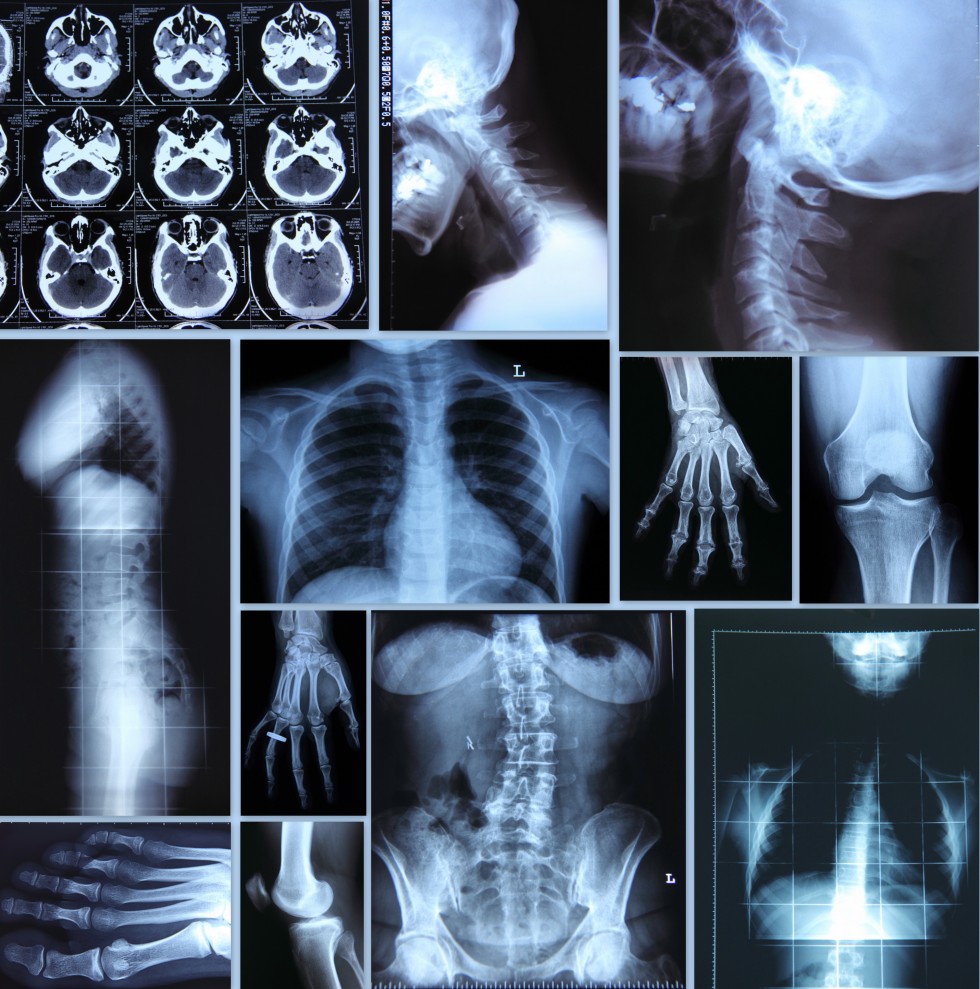

Imaging Services

The physicians of Professional Radiology, in conjunction with our partner hospitals, provide a full range of diagnostic radiology services.  We continuously investigate new procedures and techniques to better serve our patients.  We offer the latest technology and service in a variety of diagnostic areas including:

• X-ray/fluoroscopy

• Magnetic Resonance Imaging

• Computed Tomography